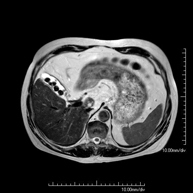

- RM d'Abdomen

Prova diagnòstica no invasiva que consisteix en l'obtenció d'imatges d'alta definició anatòmica de l'abdomen mitjançant l'ús d'un camp electromagnètic i ones de ràdio (amb un emissor i un receptor). No utilitza radiació ionitzant. En aquesta exploració s'inclouen el fetge, el pàncrees, la melsa, la via biliar, la vesícula biliar, les glàndules suprarenals, els ronyons, l'aorta abdominal, la vena cava inferior, l'estómac, el duodè, etc. En alguns casos caldrà emprar contrast paramagnètic (Gadolini) per caracteritzar les lesions. - RM Pelvis femenina